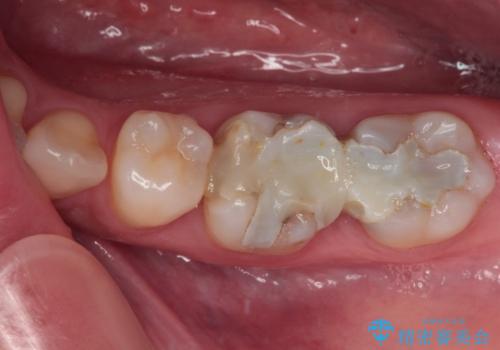

仮詰めのまま処置が進まないので転院 奥歯のむし歯治療

- 奥歯のむし歯処置を行っていたものの、しみて痛みが続く状態での経過観察が続いていたため、転院を希望して来院された患者様です。

痛みが続いているとのことで、むし歯が神経組織に及んでいる可能性があるため、処置を行うに当たりラバーダムによる唾液の排除を行うこととしました。